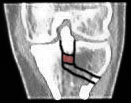

Immerhin scheinen meine Knochen eine Art Schnellheilungsmechanismus zu haben: Nur 5 Wochen nach der Korrekturoperation ist der Knochen schon fast wieder ganz verheilt - im folgenden Bild aus dem Inneren des Knies ist links das Bild vom 3. Mai, rechts jenes vom 7. Juni. Das versetzte Stück der Eminenz ist fast wieder fest drin; die Lücke beim Pfeil hat sich deutlich verkleinert - Krücken ade, Schmerzen leider noch nicht ganz. Das Streckdefizit beträgt immer noch 12 Grad.